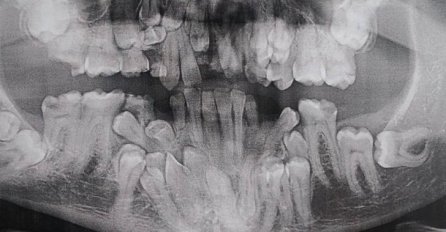

Kiosk 21.01.21. 11:58 OTIŠAO KOD ZUBARA DA SNIMI RENDGEN ZUBA, kad su ovo vidjeli uhvatili se za glavu: Ovi ljudi su ostavili svijet u čudu, A ČEKAJTE TEK DA VIDITE SLIKU BROJ 2! Saznaj više